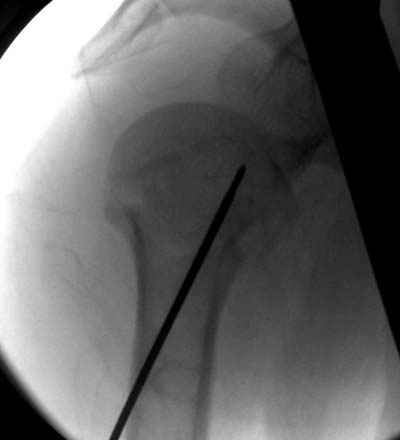

Женя, а как ты водишь спицы, в смысле, как делаешь входное отверстие, и как в него проводишь V-спицу? А то о дна из спиц, та, у которой не дошла до головки одна палочка буквы V, как-то выглядит на рентгенограмме, как будто или через очень большое отверстие введена, или каждая половинка через отдельные отверстия.

Спицы провожу по передней и задней поверхностям плечевой кости через 4,5 мм отверстия на разных уровнях.

Уточни - обе части буквы V вводишь в одно отверстие? А то по снимкам выглядит, что в разные.

V-спица проводится через 4,5 мм отверстие. Видимо, из-за разной длины вторая половина спицы *пролетела* мимо отверстия, что и привело к вторичному смещению костных фрагментов.